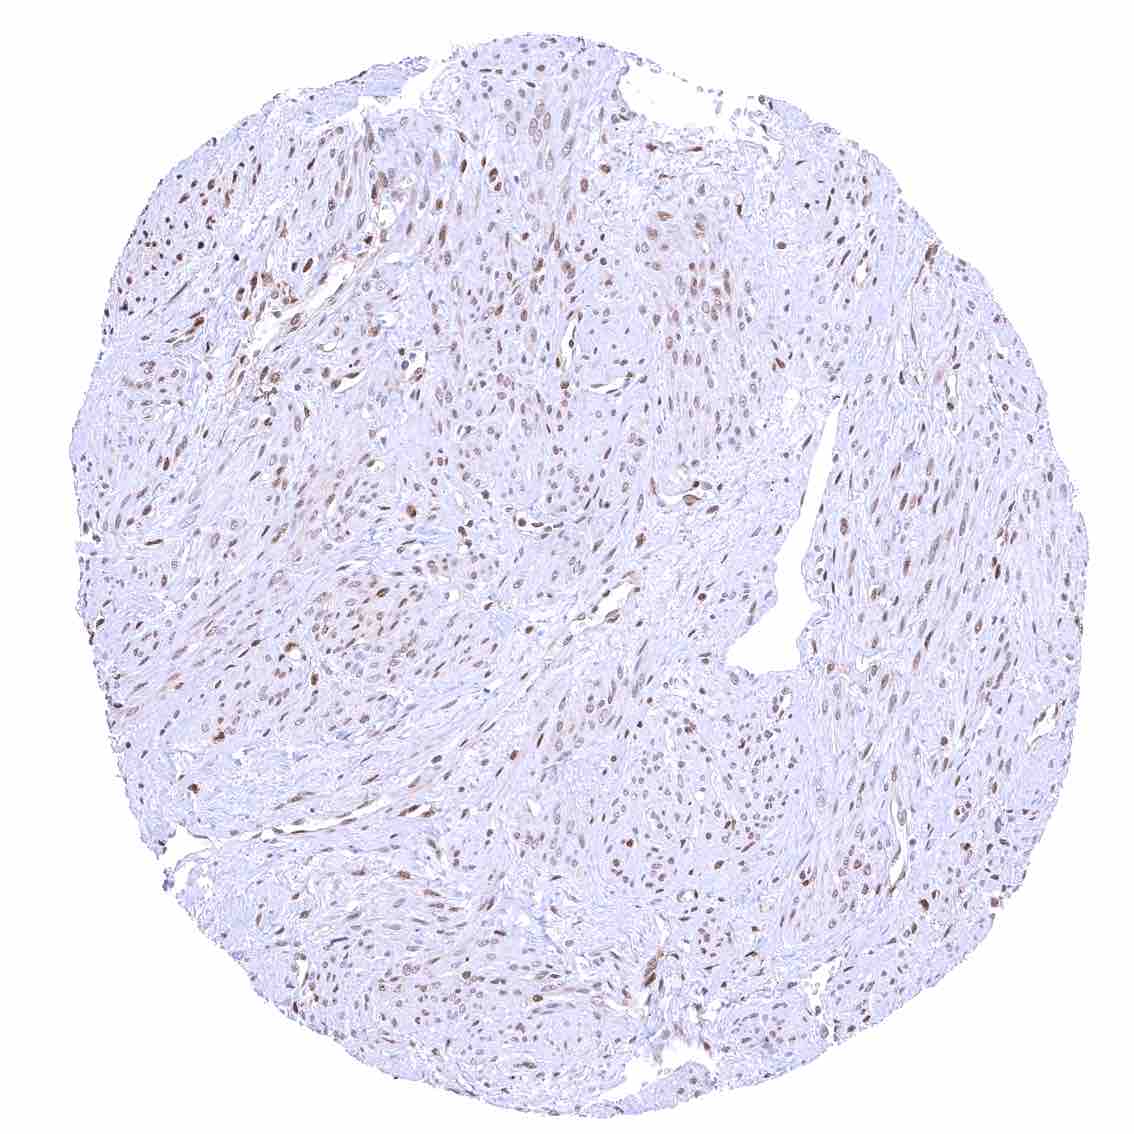

Uterus, myometrium – Nuclear p27 staining of variable intensity in most muscle cells. .jpeg